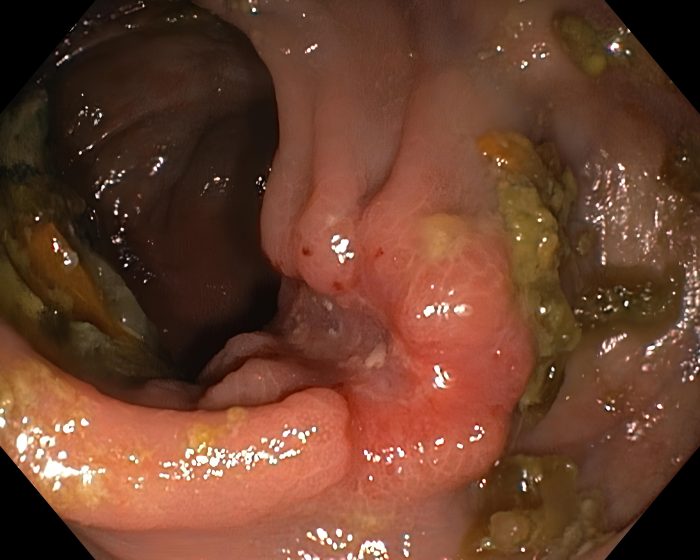

Small saucer-shaped carcinoma of the ascending colon – a typical parody embryo

Endoscopic image of a typical parodied embryo – an endophytic cancerous tumor with a rapid growth rate (ascending colon).